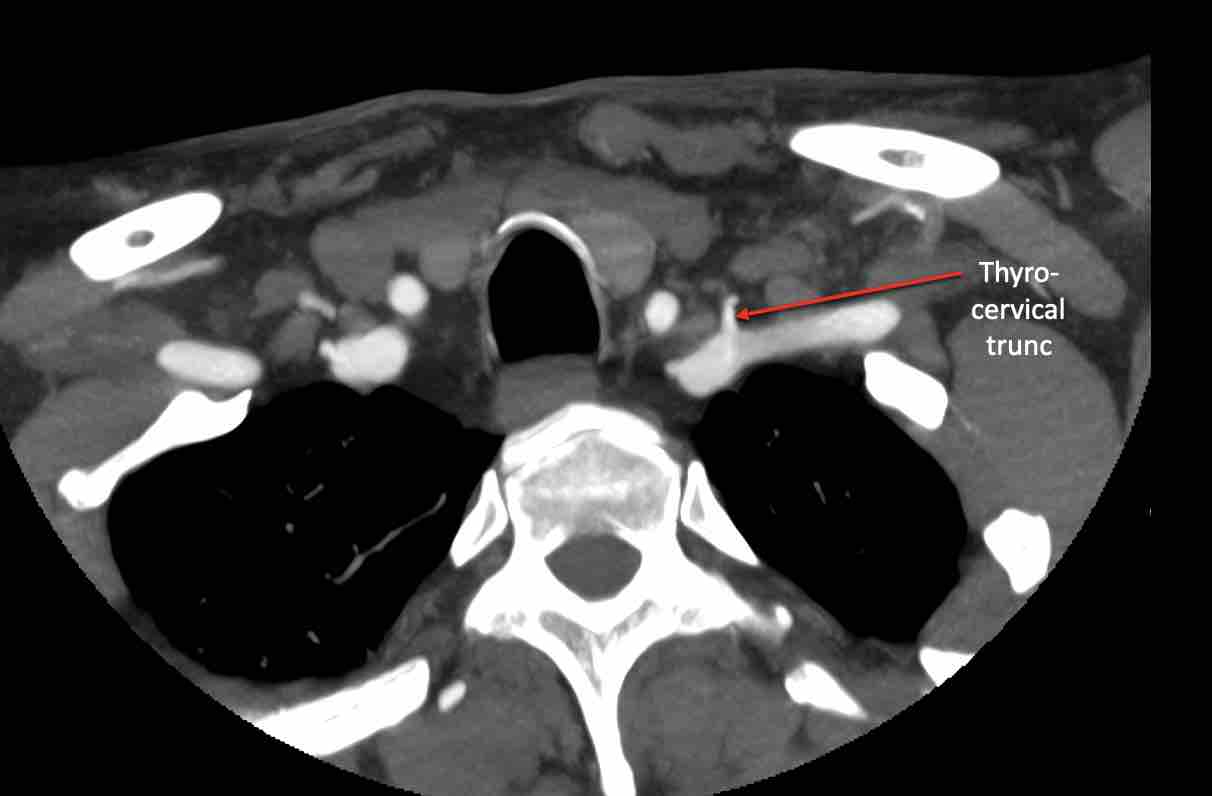

Động mạch cổ ngang

Cuộn qua các hình ảnh để xem giải phẫu của động mạch cổ ngang.